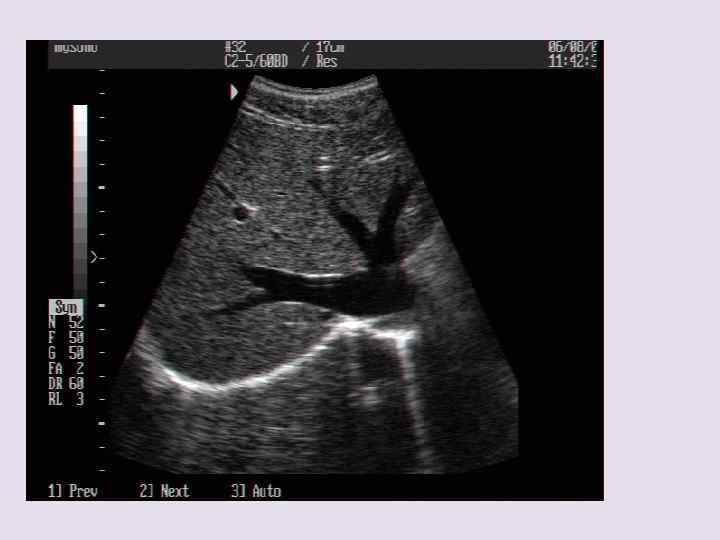

В-режим • 2 D эхография • От слова brightne-яркость. При ультразвуковом исследовании в В-режиме получается черно-белое изображение анатомических структур с различными по яркости деталями в режиме реального времени. Высота амплитуды при этом соответствует степени яркости серого цвета. Подобная регистрация эхо-сигнала дает изображение в одном измерении. Отдельные изображения сохраняются в течение короткого времени. За счет перемещения акустической оси пьезоэлементов на экране отображается обобщенная картинка среза. Затем отдельные строчки суммируются на мониторе как двухмерное изображение. На основе такого изображения можно определить параметры (размеры, объемы) исследуемого объекта. В-режим используется практически во всех областях медицины.

УЗИ брюшной полости